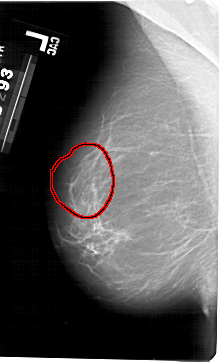

A_1493_1.LEFT_CC

LEFT_CC LINES 5491 PIXELS_PER_LINE 3121 BITS_PER_PIXEL 12 RESOLUTION 43.5 OVERLAY

FILE: A_1493_1.LEFT_CC.OVERLAY

TOTAL_ABNORMALITIES 1

ABNORMALITY 1

LESION_TYPE CALCIFICATION TYPE PLEOMORPHIC DISTRIBUTION SEGMENTAL

ASSESSMENT 4

SUBTLETY 4

PATHOLOGY BENIGN

TOTAL_OUTLINES 1

BOUNDARY